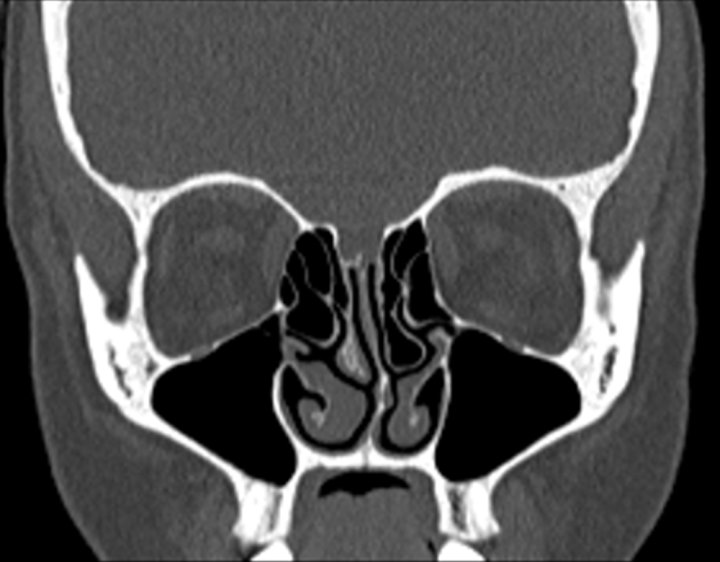

Click any image for labels.